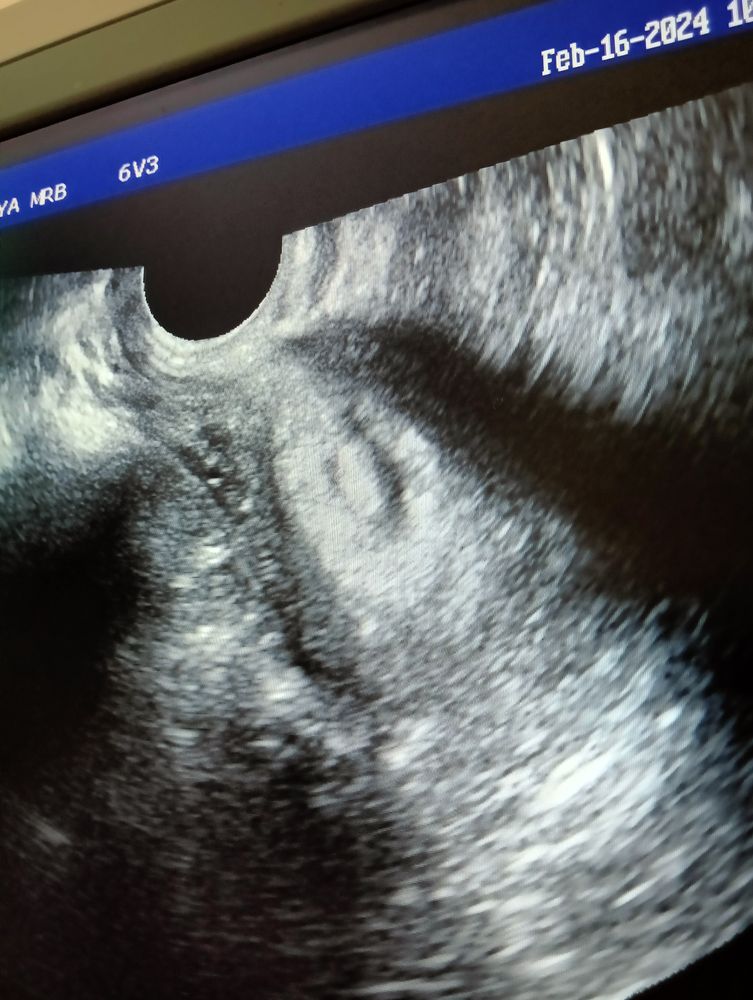

Фотки узи, от которых только грустно. И да, аппарат у нас хрень. Фото ночью не делала. Но там хоть было чётко все. 😐 Шейка матки сказали закрыта.

По моему, нормальные фотки. ПЯ видно, формы оно может быть любой, это не важно. Там даже ЖМ виднеется! Все по сроку.

Светлана, 1-2 и последняя фото - там все видно. А то что кровь мешает диагностике и под некоторыми углами не видно - ну да, так бывает, все маленькое. Аппарат плохой. Это нормально.